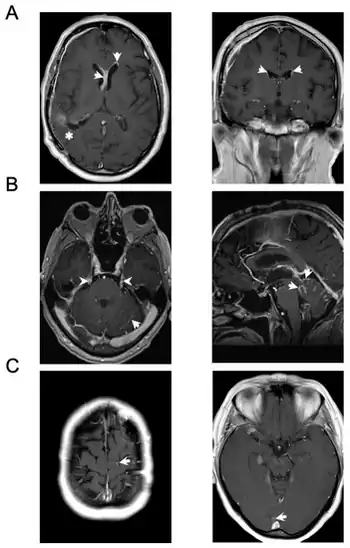

![]() | |

| Meningeal carcinomatosis: tumor cell clusters in the subarachnoid space in a brain biopsy | |